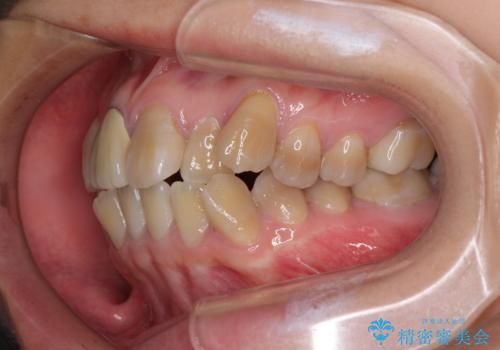

- 八重歯や前歯のデコボコを気にして来院された患者様です。

歯列が前方に傾斜しており、デコボコが強かったため、上下左右第一小臼歯4歯を抜去し、ワイヤー装置による矯正治療を行うこととしました。